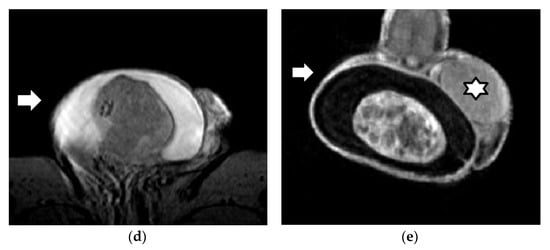

3.1. MRI Findings of TGCTs

3.2. Epidermoid Cysts